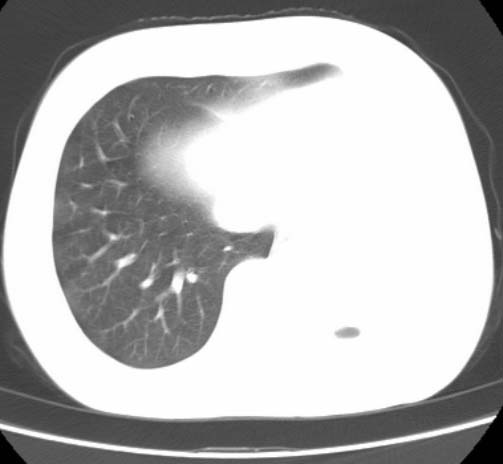

标题: CT25648:求教:是肺发育不全还是结核?

女  20岁。一月前咳血,诊“肺结核”抗痨治疗一月后,咳血停止,现复查。病人精神好。前后ct片对比未见明显变化。既往体检“正常”

1)考虑左肺结核并肺不张、支气管扩张。2)纵隔疝。

一侧肺发育不全

考虑左肺结核,左肺毁损,纵膈左偏,既往体检正常不可靠,tb一个月也不会这个样子的,有钙化,应该病程较长,冰冻三尺非一日之寒!

左肺发育不全。